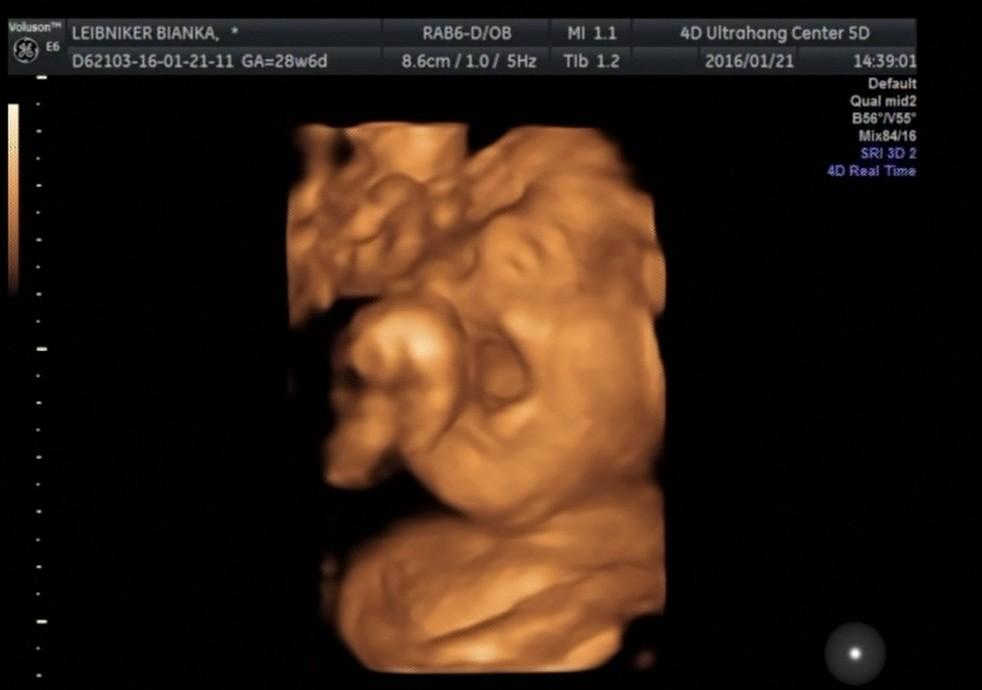

28. heti Uh Kép

Kép